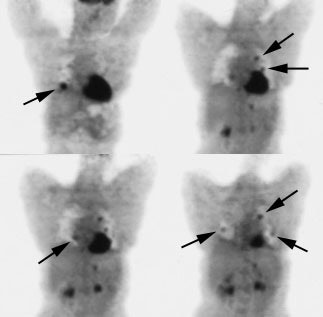

Recurrent Hurthle cell carcinoma: The patient had a history of Hurthle cell carcinoma of the thyroid. Pulmonary metastases are significantly more evident on the coincidence FDG PET examination (below left black arrows) when compared to the I131 scan (below right blue arrows). A CT scan confirmed the presence of pulmonary metastases (below). Note that a subtle bone metastasis to the high left parietal bone can be seen on I131 images. The FDG PET exam did not include this region. |